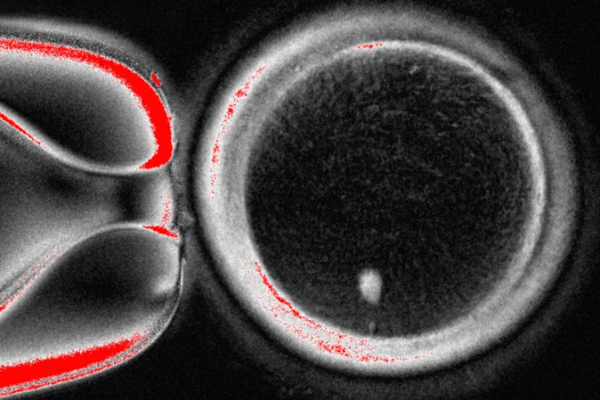

Scientists at OHSU report a lab method that uses skin cells to create functional human eggs, offering hope for future fertility treatments though clinical use remains years away.